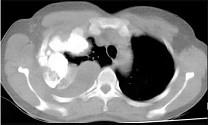

问题 男,66岁,剧烈胸痛,请结合CT图像,选择最可能的诊断 ( )

选项 A.右侧胸腔积液胸膜钙化 B.右肺癌侵犯胸膜 C.右侧胸膜间皮瘤 D.右侧肺不张 E.右侧肺肺癌

答案 C